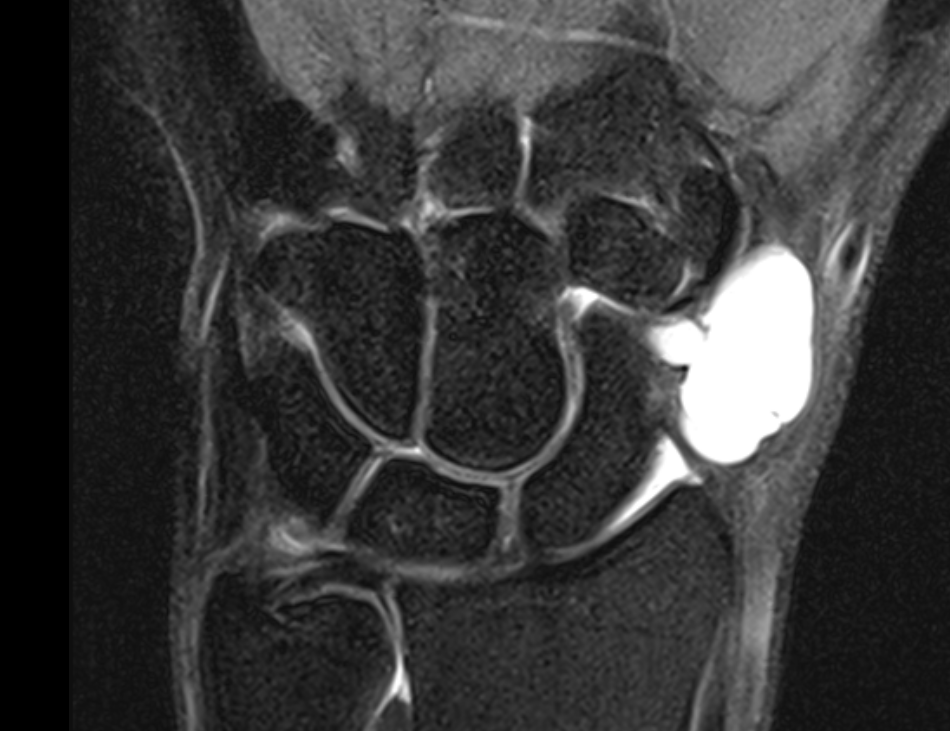

Dorsal ganglion

Dorsal ganglion arising from scapholunate joint

Dorsal ganglion arising from scapho-lunate joint